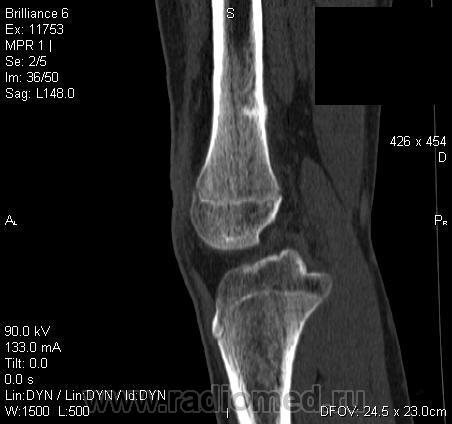

Мальчик 15 лет. Несколько месяцев назад начали беспокоить боли в коленных суставах. Травмы не было. Ребёнку был выставлен диагноз: болезнь Шлаттера, назначено лечение. На фоне лечения отмечалось значительное усиление болей, боли локализовались в левом коленном суставе. При дообследовании выявлена следующая рентгенологическая картина. Наши рентгенологи настаивают на срастающемся переломе. Но: 1) перелом без травмы? 2) бедро так не ломается

В голову приходит остеомиелит или опухоль.

Линейный периостит, уже должен был рентгенологов насторожить.

Локальный гиперостоз, выраженный болевой синдром, структура губчатого вещества диафиза не изменена наводит только на остеойд-остеому.

Я бы на первое место поставила патологическую перестройку, так называемый, стрессовый перелом. Мальчик чем-нибудь занимается?

Согласна с Ola-la - рентгенологическая картина более всего соответствует стрессорному перелому, хотя для него характерна локализация в б/берцовой кости. Меня однако, смущает и настораживает клиника - это как раз тот случай, когда я бы не дала 100% гарантии, что так не может манифестировать остеосаркома... Поскольку другие методы (МРТ, сцинтиграфия) вряд ли помогут, я бы взяла пациента на короткое ( 2недели - месяц) динамическое наблюдение.

Да, на мой взгляд, состояние после обычного "травматического перелома" (трещина), не думаю, что имел место "патологический перелом", так как костная ткань "патологически изменена" минимально. "Перистальная реакция"локальная тоже есть, на КТ "локальная  зона склероза" - все это свидетельствует именно об этом. Хотя в памяти у меня хорошо отложился Ваш последний случай о локальном утолщении кортикального слоя, когда "яйца в гнезде" еще не было. То, что анамнестически "травмы не было" - ничего не значит. Вы, по всей видимости, тоже часто встречались с такими случаями, когда ребенок не акцентировал внимание на "травме", как таковой, хотя клиника есть, боль есть. Конечно, рентгенограммы - не дай бог - ни скиалогии, ни структуры.

Буквально заключение гистологов передать не могу (мой недочет, нужно было сразу выложить на сайтОй-ой-ой), но приблизительно помню - данных за специфический процесс нет, картина консолидирующегося перелома.

Так что, по всей видимости, это действительно был стресс-перелом. Который крайне редко встречается. Хоть статейку в журнал пишиУлыбаюсь.